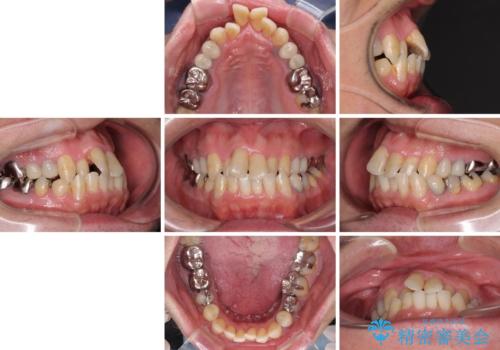

- 飛び出している上顎前歯と、奥歯に多くある銀歯を気にして来院された患者様です。

マウスピースで矯正を行いたい反面、一旦早めに前歯を整えたいというご希望があったため、まずは上顎前歯をワイヤー装置で整え、その後インビザラインにて仕上げていくこととしました。

矯正治療後には、奥歯の銀歯をすべてセラミックにて補綴治療することとしました。

ワイヤー矯正を併用したことで、上顎前歯はあっという間に整いました。

補綴治療にあたり、痛みのある歯に対して根管治療を行うこととしましたが、処置が必要な歯が多かったため、期間を要しました。

補綴治療中に前歯のデコボコが戻ってしまったため、補綴治療後にインビザラインを1セット追加して仕上げました。